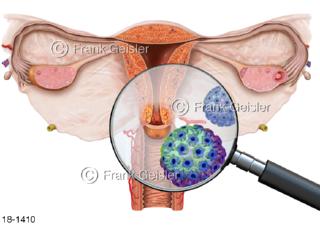

18-1410 Zervixkarzinom Gebärmutterhalskrebs, Erreger Humane Papillomaviren HPV